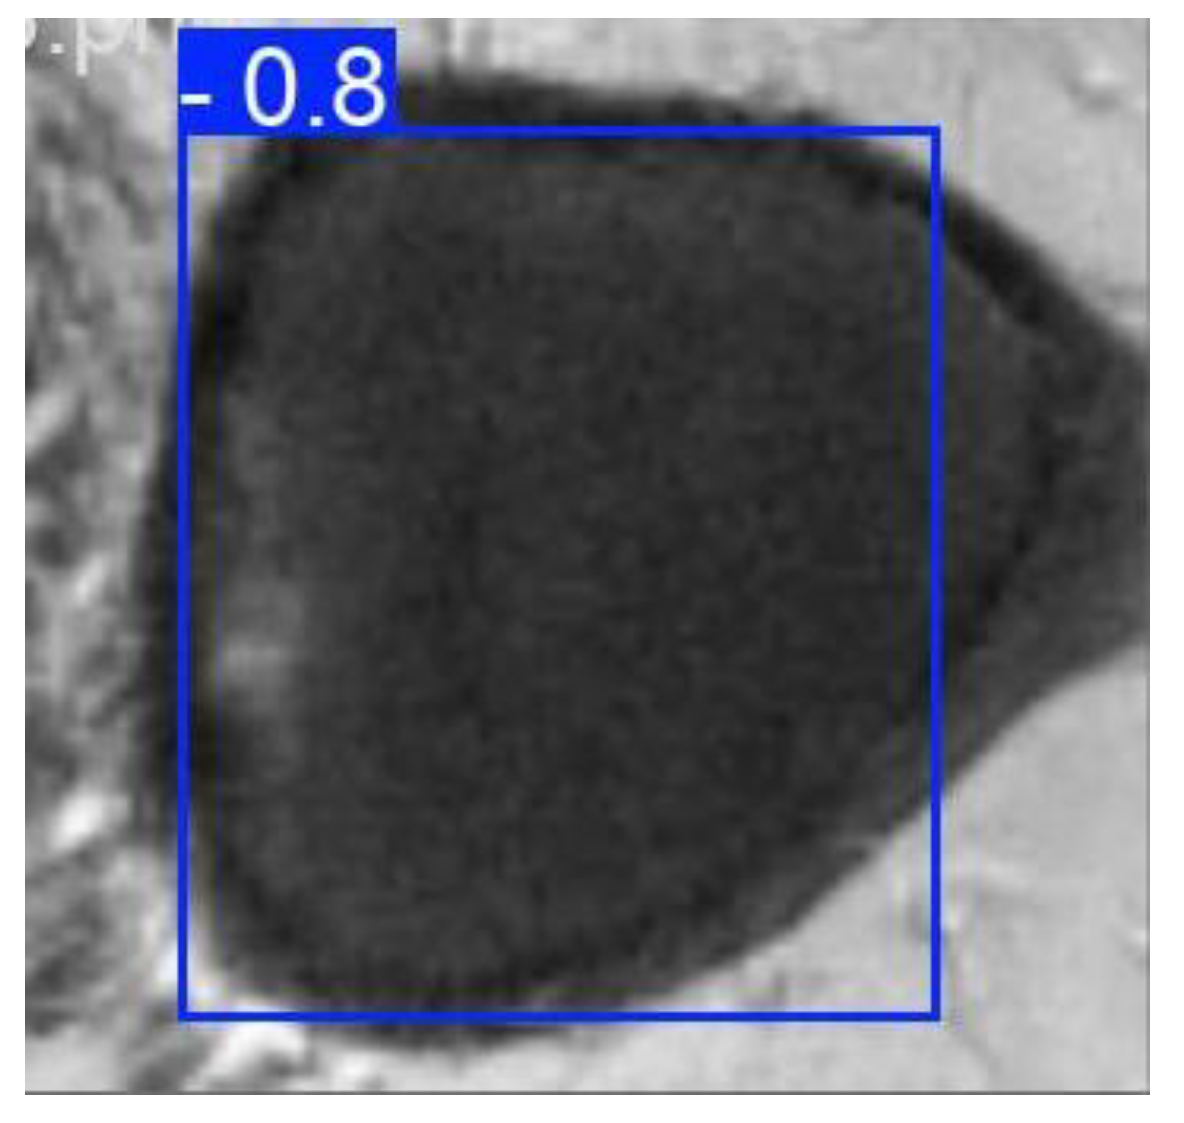

Object detection in an image involves determining the location of an object of a given class if it is present in the image. The location of an object is determined by enclosing the object in certain boundaries, most often in a bounding box. Detection is often applied to medical problems to highlight an area of interest in the context of various tasks, for example, an area containing an organ or a tumor. The development of detection architectures has progressed from basic convolutional networks, such as R-CNN, to more complex ones, such as YOLO in its various versions [30,31]. An example of determining the prostate area in an image is shown in Figure 2.

Figure 2. Example of detection using YOLO.